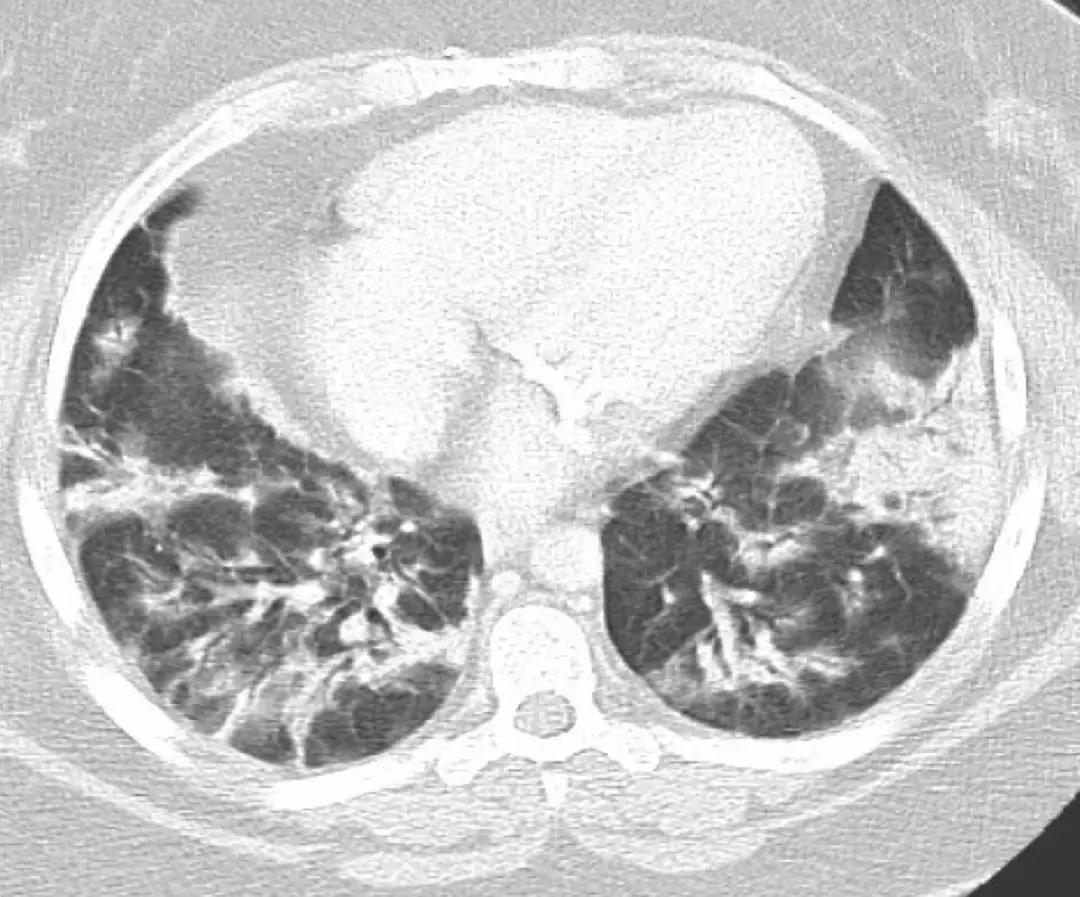

OP的影像表现:实变(周围、沿支气管血管束):80~95%;磨玻璃影:60~90%;小叶间隔增厚:55%;「反晕征」:20%;结节或团块:15~50%;还有「游走性」的特点。

实变:

中心型

混合型

磨玻璃影:

GGO合并带状实变

GGO,合并周围型及带状实变